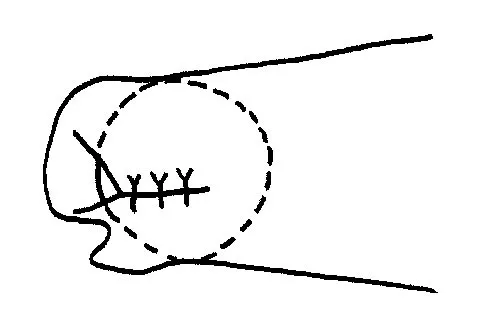

Question 39High Yield

A 42-year-old woman with a long-standing history of rheumatoid arthritis undergoes total shoulder arthroplasty for persistent pain that has failed to respond to nonsurgical management. Intraoperative radiographs reveal an oblique, minimally displaced fracture of the greater tuberosity. Based on these findings, what is the best course of action?

Explanation